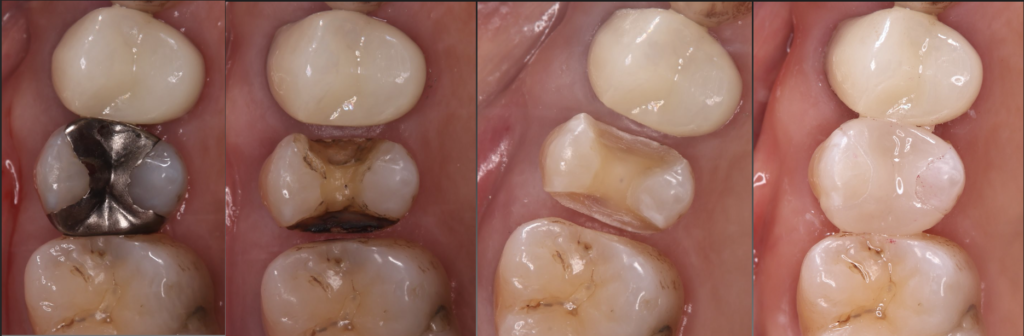

参考例

初診時の口腔内写真

当院でもこのような術前の写真を撮影し、個々の歯の虫歯、歯周病の状態、お口の全体の、歯並び、噛み合わせの状態などについてもご説明しております。写真を使って、目で実際に見ることで、話で説明を聞くだけよりも理解力が上がり、自身の歯やお口のことについて理解が深まりやすいと思います!

またこのように、治療中の写真なども撮影しながらより自分の歯がどういう状態からどういう状態になったのかを目で見て理解していただきながら治療を受けていただくことでより安心して通院していただけると思っています。